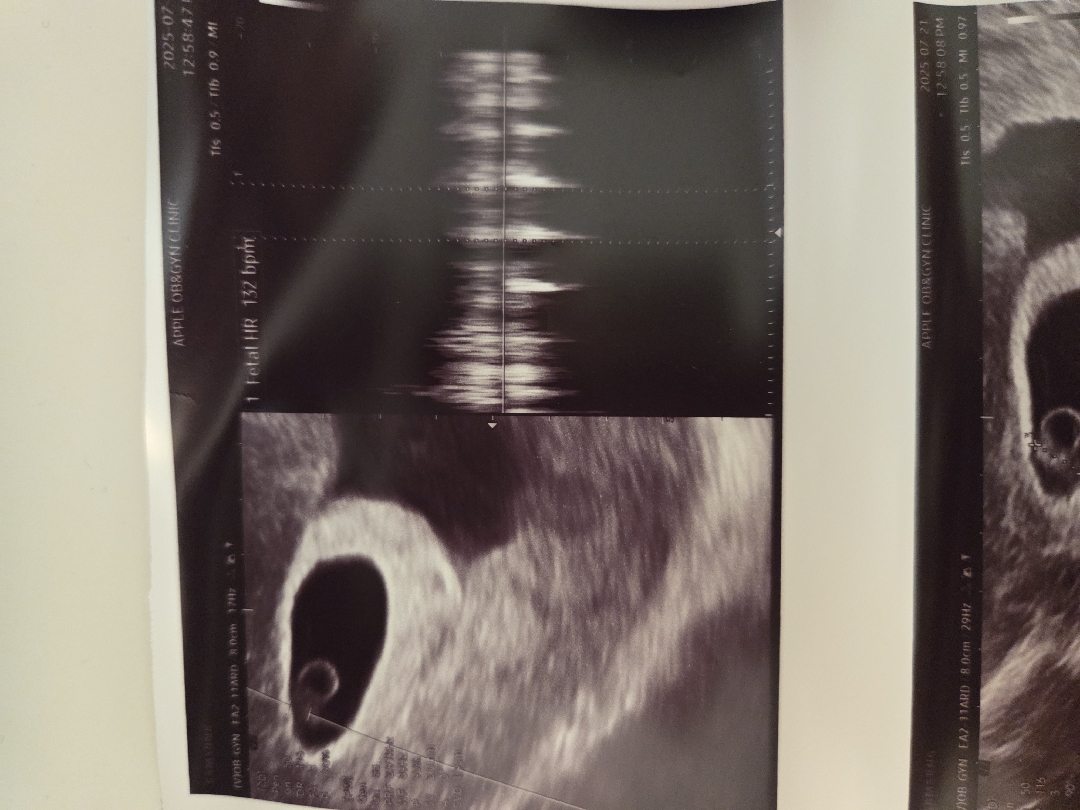

심장소리 듣고 왔어요

132bpm으로 아주 건강하다고 합니다 ㅎㅎ 피고임이 있어서 안정도 취해야 한다고 그러시네요 심장소리는 말발굽소리던데,, 그럼 딸인가요??

6주1일입니다 ㅎㅎ 감사해요